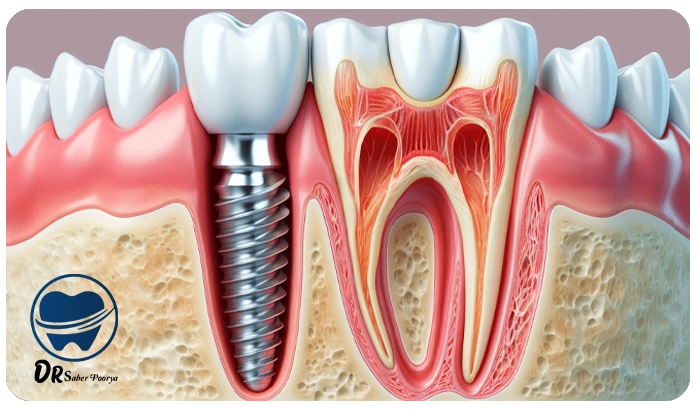

ایمپلنت دندان، به زبان ساده، یک پایهی فلزی کوچک است که به جای ریشهی دندان در استخوان فک قرار میگیرد و بعد از جوش خوردن با استخوان، تاج دندان مصنوعی روی آن نصب میشود.

مراحل انجام ایمپلنت؛ از مشاوره تا لبخند جدید

- قرار دادن پایه ایمپلنت در فک

- مدت زمان جوش خوردن (بین 2 تا 4 ماه)

- نصب روکش دندان